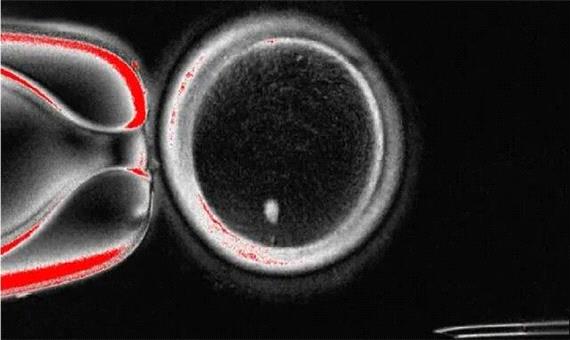

سیاست و بازاریابی - ایسنا / سلول‌های پوست انسان در یک مطالعه جنینی به تخمک تبدیل شدند و امید به باروری را افزایش دادند.

محققان دانشگاه «OHSU» روش جدیدی به نام «میتومیوز»( mitomeiosis) را برای تبدیل سلول‌های پوست به تخمک، جهت مقابله با چالش‌های ناباروری ابداع کردند.

به نقل از آی‌ای، یک نقطه عطف علمی که زمانی غیرممکن تصور می‌شد، محقق شده است. محققان دانشگاه علوم و بهداشت اورگان(OHSU) روشی را اثبات کرده‌اند که سلول‌های پوست را به تخمک‌هایی تبدیل می‌کند که قادر به تولید جنین‌های اولیه انسان هستند.

این پیشرفت، مسیر جدید بالقوه‌ای را برای درمان ناباروری از طریق گامتوژنز(gametogenesis) آزمایشگاهی (فرآیند ایجاد تخمک و اسپرم در خارج از بدن) ارائه می‌دهد.

دانشمندان به جای برنامه‌ریزی مجدد سلول‌های بنیادی به گامت، از انتقال هسته سلول سوماتیک استفاده کردند، همان رویکرد اساسی که نخستین گوسفند شبیه‌سازی شده دنیا را در سال 1997 به دنیا آورد.

آنها هسته یک سلول پوست را به یک تخمک اهدایی که هسته آن جدا شده بود، پیوند زدند. سیتوپلاسم تخمک اهدایی باعث شد هسته سلول پوست نیمی از کروموزوم‌های خود را دور بریزد و «میوز» را تقلید کند.

نتیجه، یک تخمک هاپلوئید بود که می‌توانست از طریق لقاح مصنوعی(IVF) استاندارد با اسپرم لقاح داده شود و جنین‌هایی با ورودی ژنتیکی برابر از هر دو والدین تشکیل دهد.

محققان در این مطالعه، 82 تخمک عملکردی تولید کردند و آنها را با اسپرم لقاح دادند. در حالی که اکثر آنها در مرحله 4 تا 8 سلولی به دلیل ناهنجاری‌های کروموزومی متوقف شدند، حدود 9 درصد روز پس از لقاح به مرحله بلاستوسیست رسیدند.